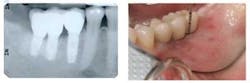

Click here to see figures larger.Diagnose the X-RayHere is our first of a series of images for you to help identify the problem. Please respond to be included in thedrawing for a $25 gift card.What did the operator do wrong to achieve this image? E-mail [email protected] to answer.